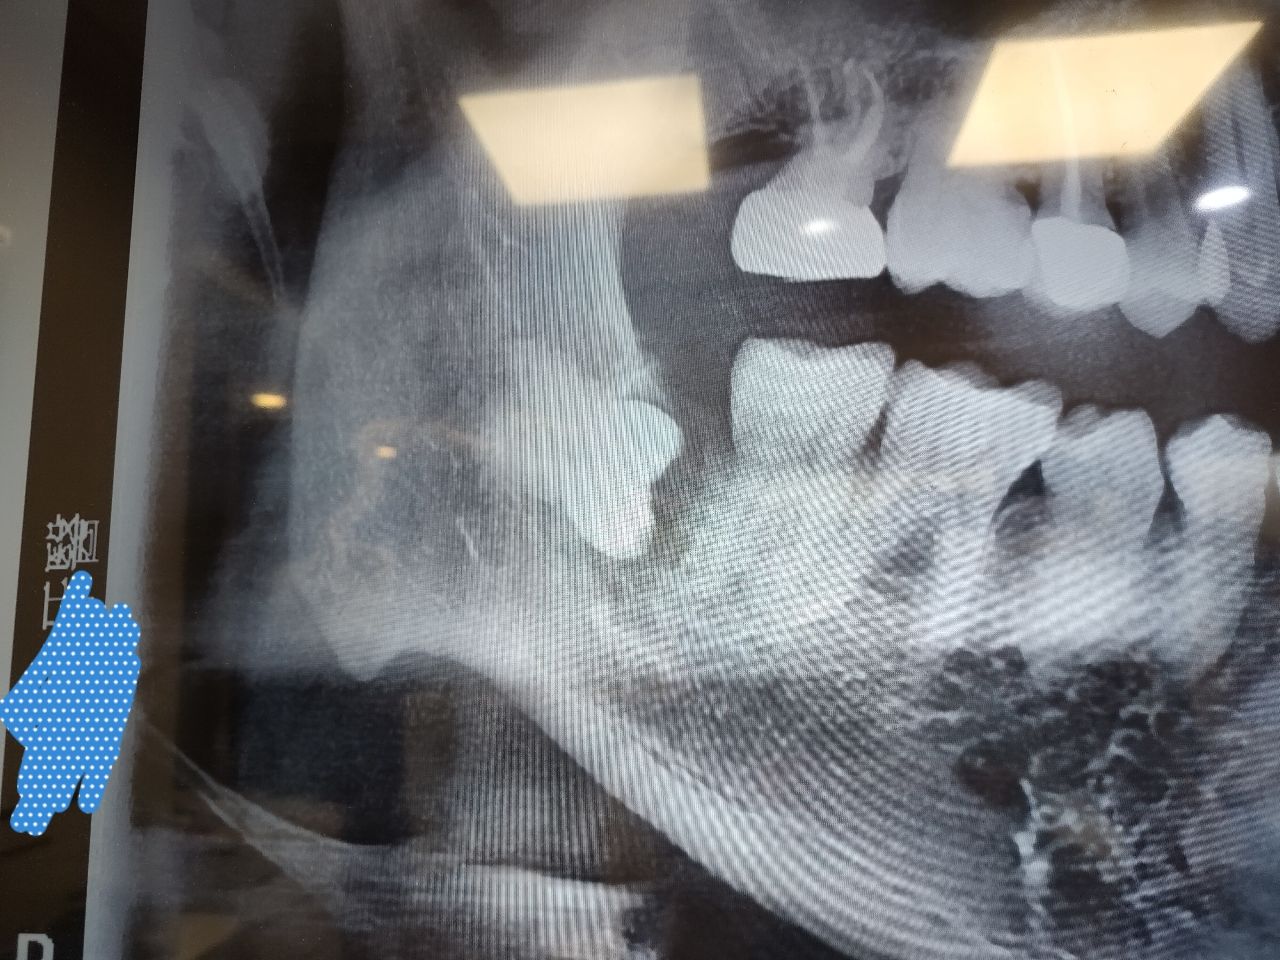

有沒有人的水平智齒

也跟我有類似的情形

是歪掉會傷到神經的這種

https://i.mopix.cc/6AVHl5.jpg

有去給大醫院評估過

醫生說是看個人自己決定